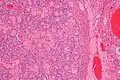

| Micrograph of a sex cord tumour with annular tubules. H&E stain. | |

Sex cord tumour with annular tubules (SCTAT) is a rare ovarian tumour in the sex cord group of gonadal tumours.

It has a distinctive appearance under the microscope, from which it derives its name.